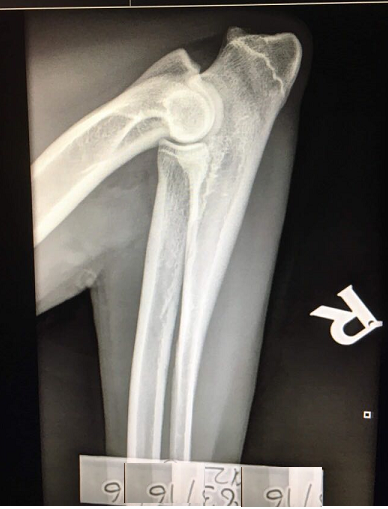

Kyynärnivelten osalta vuosina 2015-2024 syntyneistä pennuista on tutkittu 62 prosenttia. Tutkituista koirista 84 prosenttia oli täysin terveitä ja lieviä muutoksia (kyynärniveldysplasian aste 1) todettiin 12 prosentilla. Vakavampia muutoksia tavataan vähemmän.